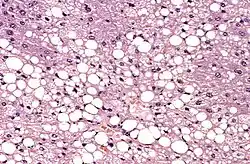

En cuestión a lípidos, el formol fija algunos lípidos complejos y no saturados, pero no actúa sobre las grasas neutras, y los fosfolípidos tienden a difundir lentamente en el fijador, por lo que el uso del formol en lípidos no es recomendado.[4]

El método de tinción de rutina es el denominado como hematoxilina-eosina (H-E). La hematoxilina es un colorante nuclear, y la eosina, citoplasmático. También existen las denominadas técnicas especiales, tal como: Gomori (para fibras de reticulina), Ziehl Neelsen (para bacilos ácido-alcohol resistentes), Grocott (para hongos), orceína (para fibras elásticas), Gordon-Sweet, rojo Sudán, negro Sudán, azul de Nilo, Golgi, etc.